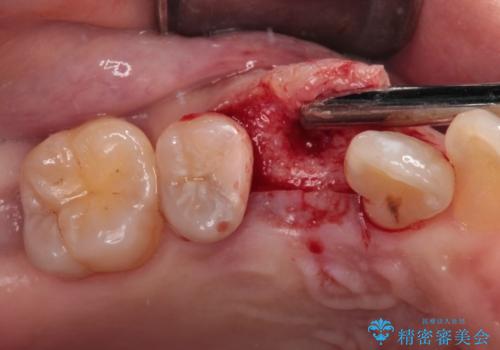

2本の歯が前後に重なった状態でむし歯となっていたので、抜歯後に歯肉や骨の状態が落ち着くのを待ち、インプラントを埋入することとしました。

崩壊した歯は全て抜去し、他人から見える位置の歯はセラミッククラウンが装着され、整った口腔環境となりました。